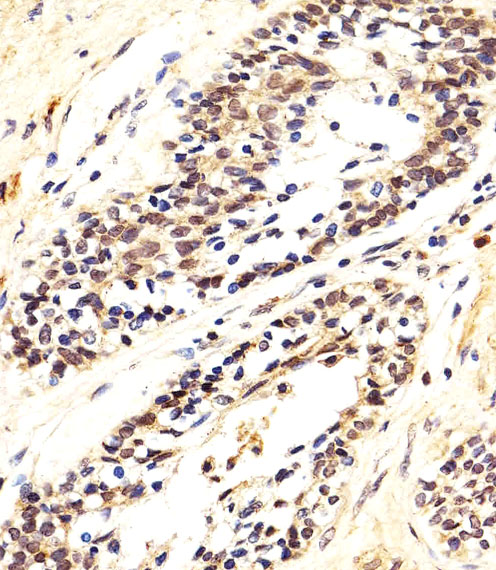

Immunohistochemical analysis of paraffin-embedded H. prostate carcinoma section using AKT1/2/3 Antibody (Center)( AMM08752G). AMM08752G was diluted at 1:25 dilution. A peroxidase-conjugated goat anti-rabbit IgG at 1:400 dilution was used as the secondary antibody, followed by DAB staining. |